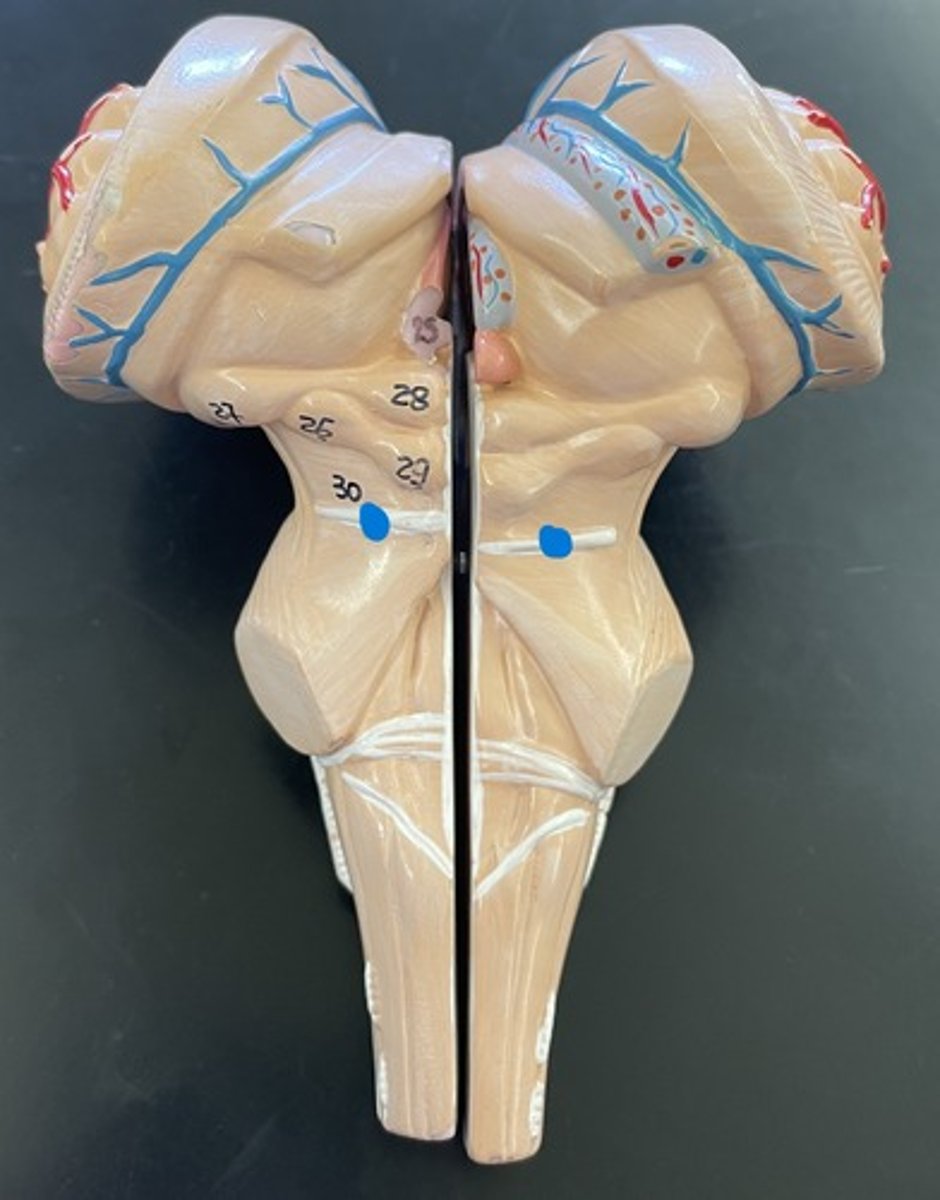

Cervical enlargement

Blue

Lumbar enlargement

Purple

Conus medullaris

Green

Cauda equina

Red

Filum terminale

blue

25